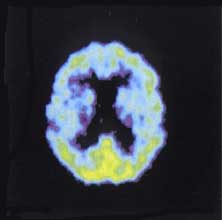

Особый интерес в плане понимания механизма действия препарата представляют данные ПЭТ-исследования с 18F-дезоксиглюкозой. У 7 пациентов (2 последствия ишемического инсульта, 2 ДЭ, 1 последствия тяжелой ЧМТ, 1 болезнь Альцгеймера, 1 рассеянный склероз) получавших терапию Болюсами Хуато, отмечалось, как локальное, так и диффузное повышение скорости метаболизма глюкозы в головном мозге, что может говорить о выраженном неспецифическом ноотропном действии препарата.

В качестве иллюстрации приведены ПЭТ снимки больной Zh-a, перенесшей ишемический инсульт в бассейне левой средней мозговой артерии за 12 месяцев до начала терапии БХ с формированием в левом полушарии постинсультной кисты. (На верхних снимках выраженный гипометаболизм в левом полушарии чем более темное, тем ниже метаболизм глюкозы. На нижних снимках улучшение метаболизма как вокруг кисты, так и диффузно во всем сером веществе головного мозга).

Zh-a, женщина 74 лет, диагноз: ишемический инсульт в бассейне ЛСМА, за 12 месяцев до исследования

Примечание: верхний ряд снимков до лечения, нижний ряд снимков после лечения

Больная К-а с дисциркуляторной энцефалопатией III стадии до лечения выраженный диффузный гипометаболизм, особенно в правом полушарии, после лечения значительное улучшение.

K-a, женщина 72 лет, диагноз: дисциркуляторная энцефалопатия III

На графиках: данные об уровне потребления глюкозы в определенных областях интереса у тех же пациенток до лечения (before) и после лечения (after) сравниваются с 95%-ным доверительным интервалом уровня потребления глюкозы (верхняя граница (M+2sd) и нижняя граница нормы (M-2sd)), полученным по данным о здоровых добровольцах. По оси X области интереса, по оси Y отношение уровней накопления радиофармпрепарата в исследуемых областях и мозжечке (в процентах).

У больной Zh-a До лечения практически все значения ниже нормы, больше это выражено в левом полушарии. После лечения кривая существенно повышается, достигая нормальных значений, как в зоне максимального поражения, т.е. вокруг кисты левая лобная доля, (зоны интереса 7-11), так и в правой лобной доле (зоны интереса 35-43, 46-47).

У больной К-а До лечения кривая расположена на нижней границе нормы или не доходит до нее. После лечения отдельные области (передние и задние отделы поясной извилины зоны интереса 13-14 и 46-47 соответственно, правая лобная доля зоны интереса 36-40) доходят до нормальных значений. В целом кривая значений после лечения выше, чем до лечения.